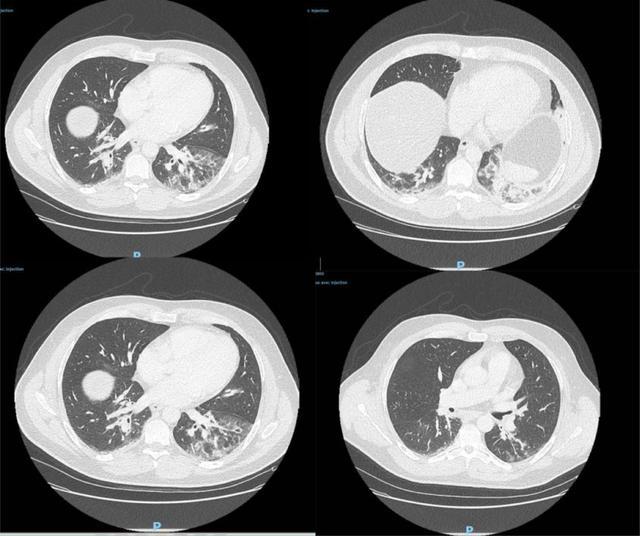

据了解,患者去年12月27日到急诊室就医,CT检查显示双侧肺下叶呈现磨玻璃影,并伴有咯血、咳嗽、头痛及发热症状,且当时症状已持续4天。病患当天被收入重症监护室并接受抗生素治疗,后因病情好转于12月29日解除重症监护。说明什么?

△图为病患CT检测影像